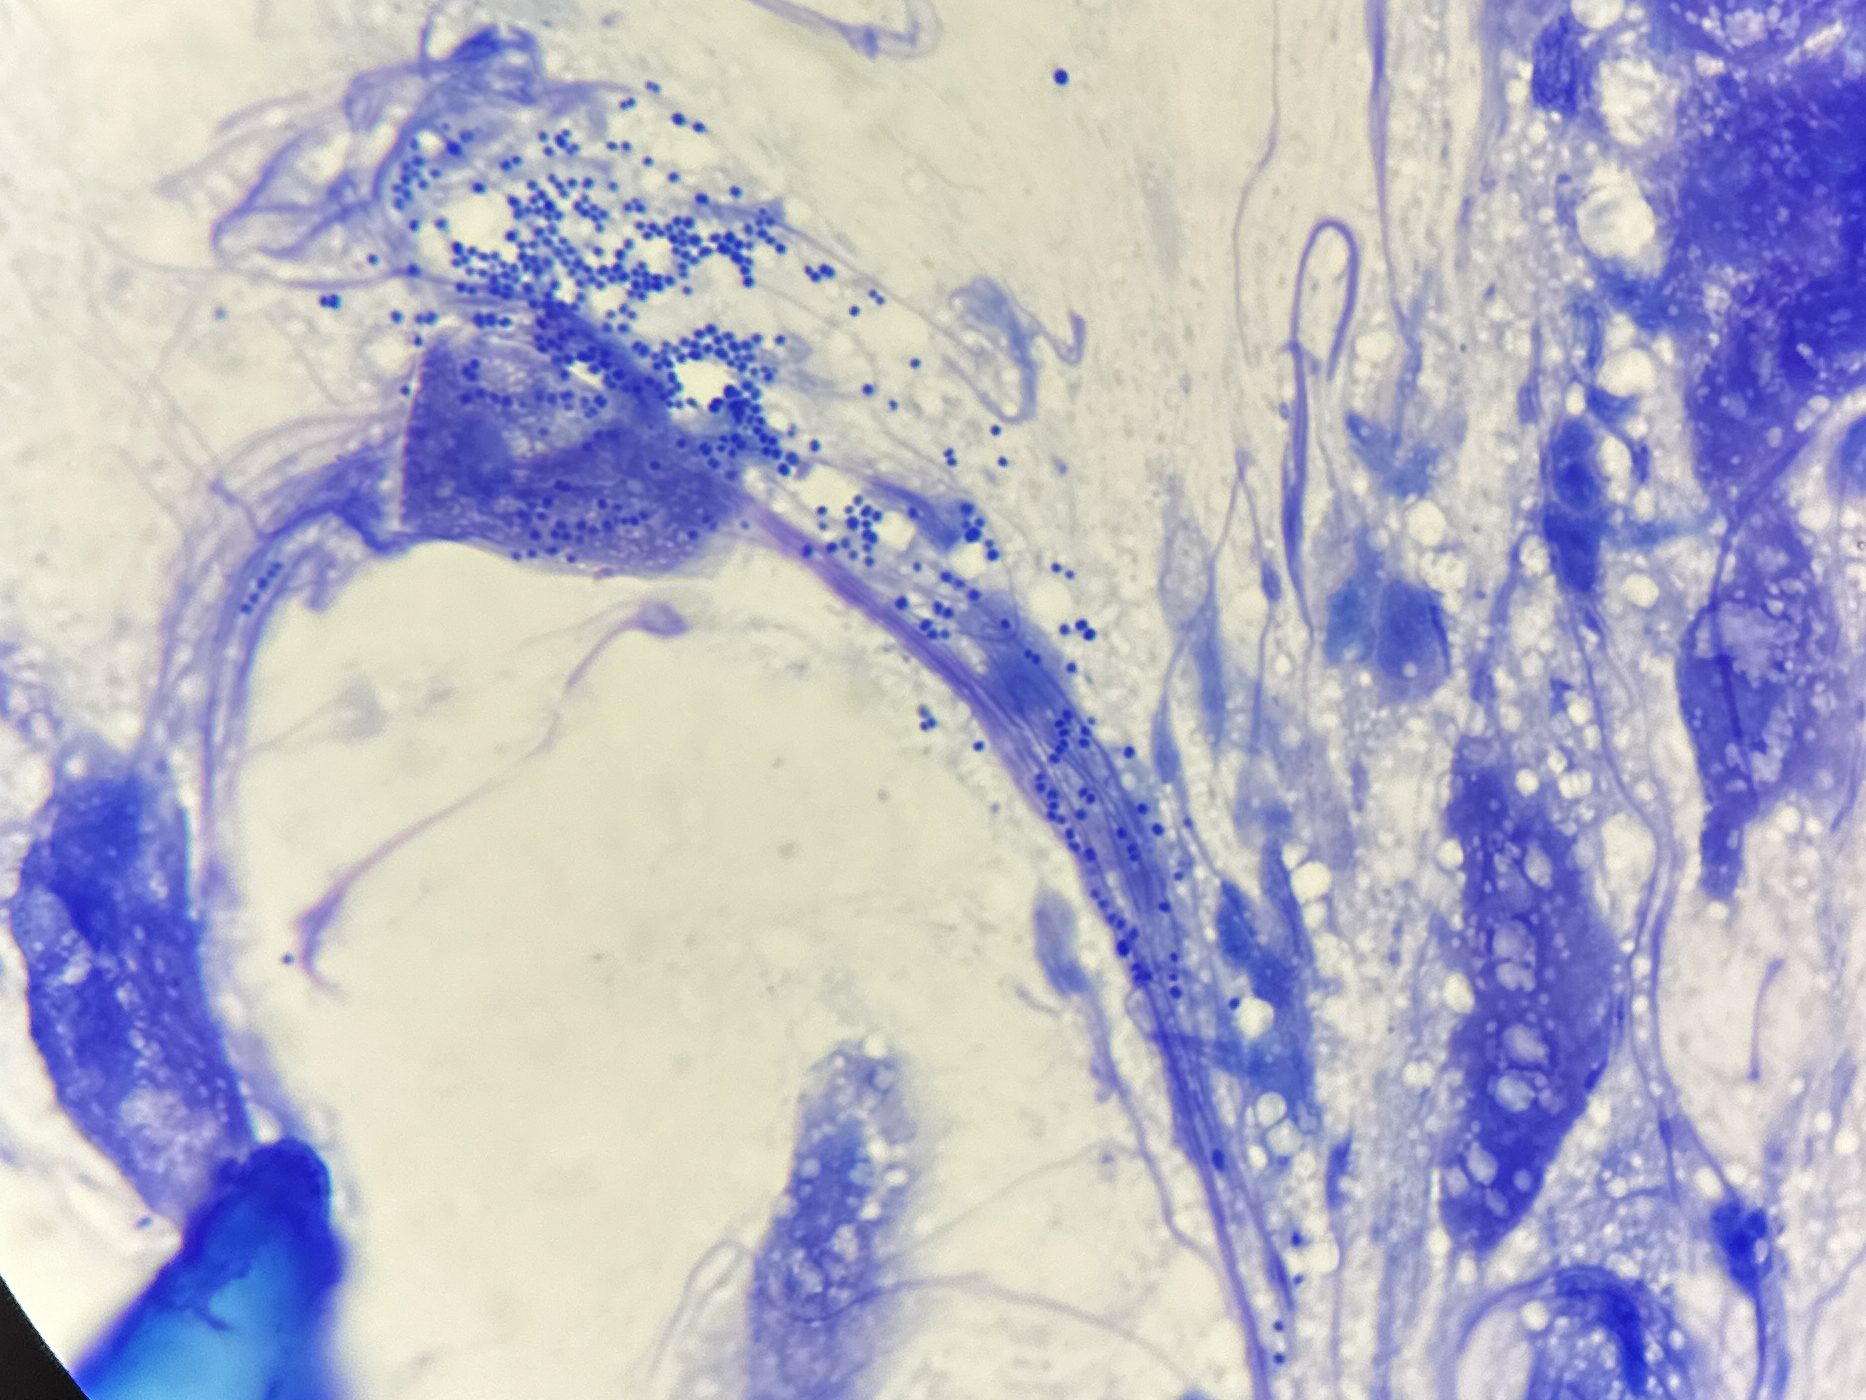

全ての膿皮症の症例で細胞診の実施が推奨されています。特に全身性抗菌薬を使用する際には、治療前後で毎回細胞診を行うことが強く推奨されます。

- 1000倍の顕微鏡観察により、膿皮症の典型的な細胞像(好中球やマクロファージ内の球菌)を確認。

- 健常皮膚でも細菌が存在するため、細菌数の閾値は存在せず、炎症細胞内の細菌が診断の鍵となります。

- また細胞外菌体およびスメア状に拡大する炎症細胞の核が認められるか、細菌過剰増殖のように炎症細胞に乏しい細菌増殖所見を認める場合も膿皮症と判断。